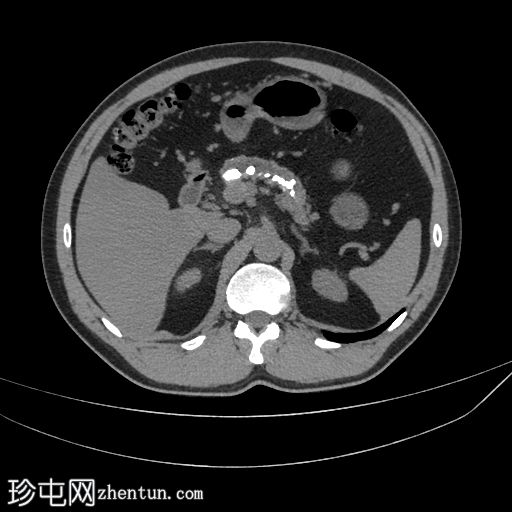

CT

轴位增强扫描(门静脉期)

胰腺萎缩、粗大钙化及主胰管扩张

无急性胰腺炎征象

肝脂肪变性

左侧结肠憩室

主胰管扩张、胰腺萎缩和钙化是慢性胰腺炎诊断的关键。该患者有反复发作的急性胰腺炎病史。